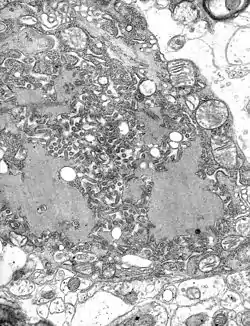

![]() TEM mikrograf med talrige rabies virioner | |